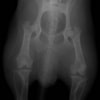

術前正面像

術後左後肢正面像

術前のTPAは左後肢33.1°右後肢26.8°でしたがTPLO実施により左後肢5.5°右後肢12°に矯正されました。

左後肢の挙上を主訴に来院されました。触診にて両関節の前方引き出し兆候、両膝蓋骨の内方脱臼を認めました。関節液検査より免疫介在性多発性関節炎は否定的でした。レントゲン検査にてfat pad signを伴う関節炎が認められたことから、前十字靭帯断裂と膝蓋骨内方脱臼(左GradeⅢ 右GradeⅢ〜IV)併発と診断し、手術を行いました。

手術は片足ずつ行い、両膝とも術中の関節鏡検査にて前十字靭帯の完全断裂と半月板損傷を確認しました。TPLO、半月板切除と滑車溝形成を始めとした膝蓋骨脱臼整復術を実施いたしました。膝蓋骨の安定化を測るために外側支帯を強固に縫合し、内側支帯は切除し縫合せずに開放状態にしています。

術後の歩行状態は良好です。